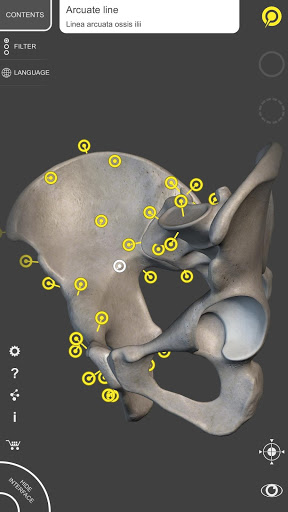

Bằng cách chọn mô hình hoặc ghim, bạn sẽ được hiển thị các thuật ngữ liên quan đến bất kỳ bộ phận giải phẫu cụ thể nào, bạn có thể chọn từ 12 ngôn ngữ và hiển thị các thuật ngữ bằng hai ngôn ngữ cùng lúc.

• Ghim tương tác cho phép trực quan hóa thuật ngữ liên quan đến mọi chi tiết giải phẫu

ĐA NGÔN NGỮ

• Các thuật ngữ giải phẫu và giao diện người dùng có sẵn bằng 12 ngôn ngữ: tiếng Latinh, tiếng Anh, tiếng Pháp, tiếng Đức, tiếng Ý, tiếng Bồ Đào Nha, tiếng Nga, tiếng Tây Ban Nha, tiếng Trung, tiếng Nhật, tiếng Hàn và tiếng Thổ Nhĩ Kỳ

• Có thể chọn ngôn ngữ trực tiếp từ giao diện của ứng dụng

• Các thuật ngữ giải phẫu có thể được hiển thị bằng hai ngôn ngữ cùng một lúc